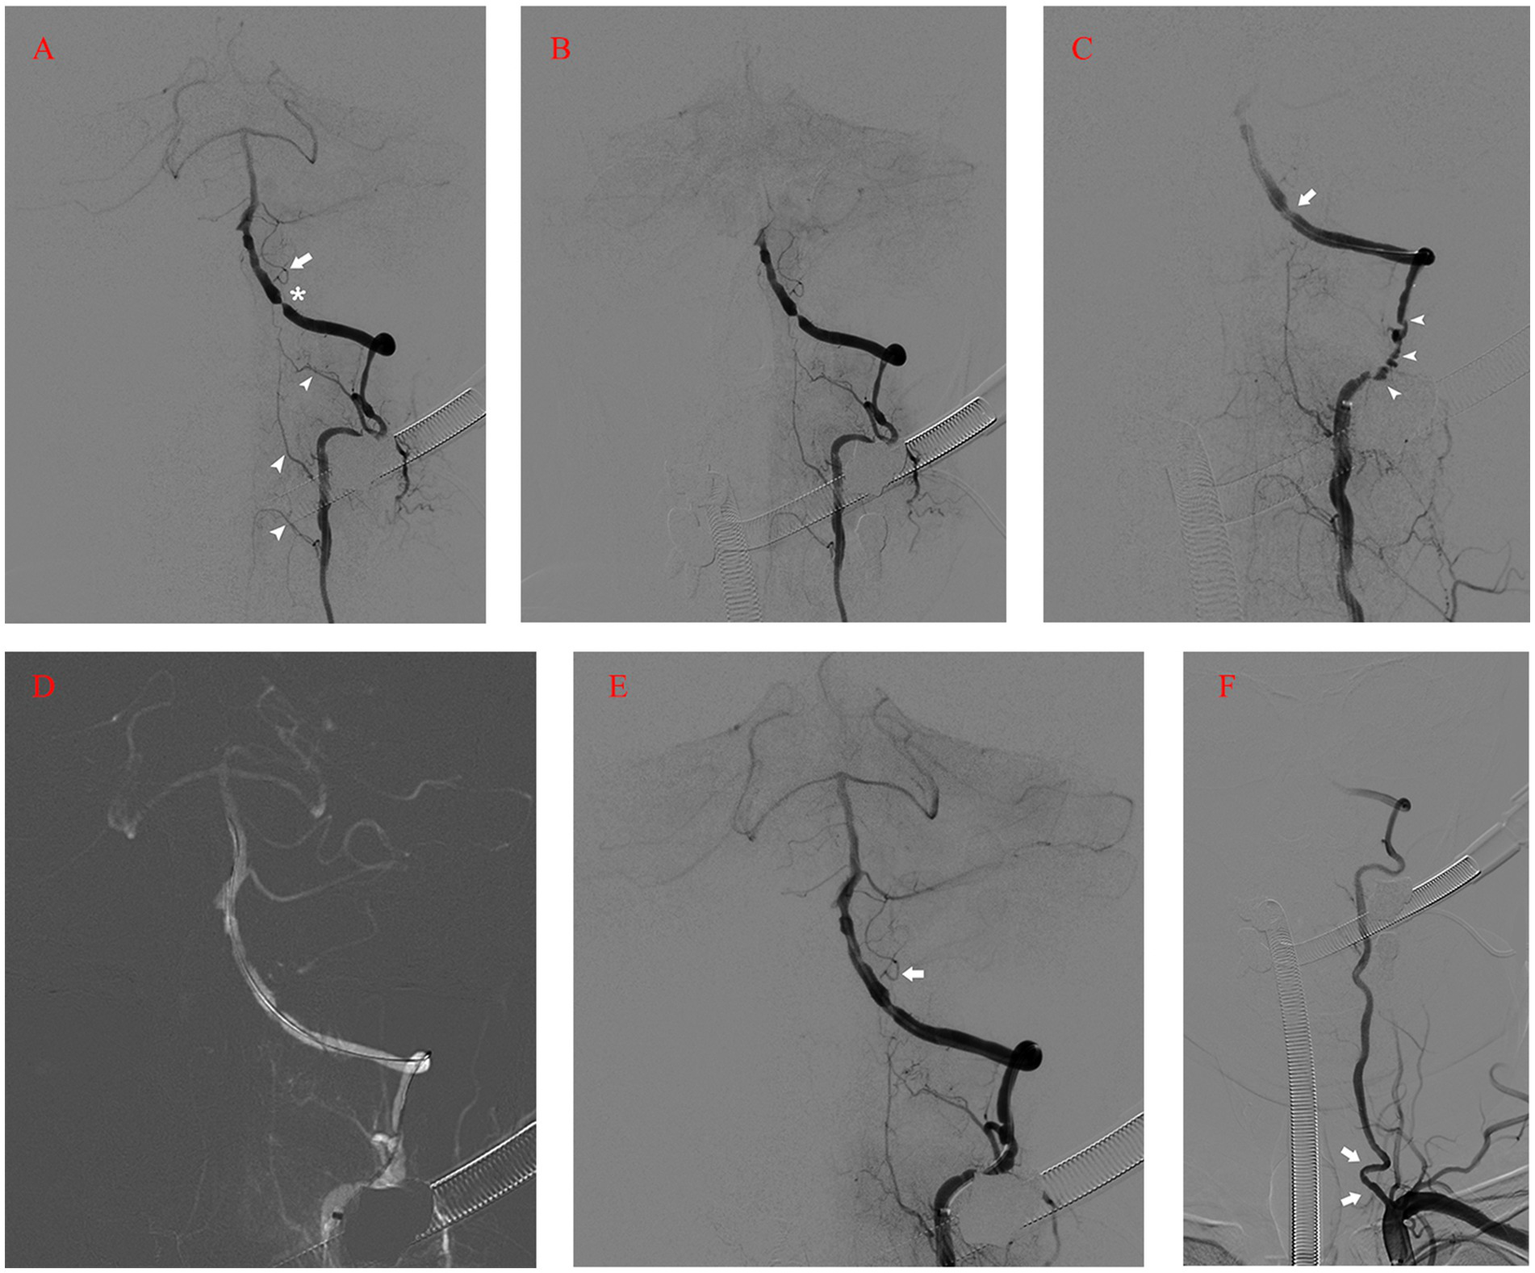

After 50 days of rehabilitation, he was brought in for endovascular treatment. Physical examination on the second admission showed grade 4+ muscle strength in left extremities. Preoperative MRI revealed no new ischemic stroke. Five days after admission, the patient’s left intracranial VA was recanalized under general anesthesia. A 90 cm 6F Neuronmax088 long sheath (Penumbra, Inc., Alameda, CA, USA) was introduced into the initial segment of the left subclavian artery. Angiography with a 115 cm 5F AXS Catalyst 5 distal access catheter (DAC) (Stryker Neurovascular, Michigan, USA) in the distal V2 segment revealed severe stenosis, dysplasia in the left posterior inferior cerebellar artery (PICA), and anastomosis supplying blood flow from the left VA to the cervical cord (Figure 2A). A concomitant clear visualization of the left VA and venous phase of the intracranial anatomy suggested that the DAC incompletely blocked blood flow (Figure 2B). A 2.25 × 9 mm Gateway balloon catheter (Stryker Neurovascular, Fremont, CA, USA) was delivered over a 300 cm synchro2 microguidewire (Stryker Neurovascular, Salt Lake, Utah, USA) to the site and slowly dilated to 7 atm. Post-angioplasty angiography revealed improvement of the stenosis and marked spasm of the left V3 segment (Figure 2C). The slow infusion of 1 mg of intra-artery nimodipine alleviated the spasms (Figure 2D). Next, a 4.5 × 14 mm Enterprise stent (Codman & Shurtleff, Inc., Raynham, MA, USA) was quickly and successfully implanted in the stenotic segment. The DAC was withdrawn immediately after the control run (Figure 2E). The final run showed only minor spasms in the initial segment of the left VA (Figure 2F). The patient showed no neurologic deterioration on awakening. Proper blood pressure was maintained using intravenous urapidil, while tirofiban was used to prevent acute stent thrombosis. Four hours later, the patient developed an occipital headache and back neck pain, mainly on the left side. Postoperative CT imaging revealed nothing significant.

Figure 2

(A) Angiography with DAC in the distal V2 segment revealing severe stenosis (asterisk), dysplasia in the left PICA (arrow), and anastomosis supplying blood flow from the left VA to the cervical cord (arrowhead). (B) Left vertebral angiogram showing the venous phase of the intracranial anatomy and left VA flow arrest. (C) Post-angioplasty angiography revealing the improvement of the stenosis (arrow) and marked spasm of the left V3 segment (arrow-head). (D) Roadmap after intra-artery nimodipine showing the spasm mitigation process. (E) Control run after the deployment of Enterprise stent showing the patency of the left VA and PICA (arrow). (F) The final run showing the minor spasms in the initial segment of the left VA (arrow). DAC, Distal Access Catheter; PICA, Posterior Inferior Cerebellar Artery; VA, Vertebral Artery.

Matsubara reported a case of ruptured VA dissecting aneurysm treated with internal trapping. The patient developed concomitant medulla oblongata and cervical cord infarction postoperatively, with a poor outcome. The author attributed the complication to the obstruction of perforating arteries supplying the medulla oblongata and ischemia of the spinal artery branches originating from the left VA (7). The upper medulla oblongata is supplied by a pair of anterior spinal arteries originating from the VA. The lateral region of the medulla oblongata is perfused by PICA or VA, while the posterior part is perfused by the posterior spinal artery, which originates from the VA or PICA (8). Tsuruta et al. found that intraoperative proximal flow arrest was performed in all four symptomatic infarction cases of VA dissecting aneurysm embolization. They believe that a long segmental flow arrest carries the risk of collateral circulation insufficiency and thromboembolism, resulting in medulla oblongata and cervical cord infarction (9). We used DAC to provide both steady proximal support and proximity to stenosis during the operation. However, blood flow was arrested in a long VA segment (Figure 2B) due to its tortuosity. Although we rapidly withdrew the DAC after the quick and necessary manipulations and restored blood flow (Figure 2E), reperfusion injury was initiated instead of complete infarction.

Therefore, in our case, all the branches mentioned above, supplying the left medulla oblongata and cervical cord, might have been affected due to the flow arrest in the left VA. It is likely that the temporary obstruction of perforating, anterior spinal, and posterior spinal artery branches arising from the left VA, resulting from the flow arrest by the DAC through tortuous vasculature, led to a short ischemia period and subsequent reperfusion injury. Notably, after the pass of the balloon catheter, we observed significant spasms in the V3 segment (Figure 2C). Although intra-artery nimodipine mitigated the spasms, this minor reperfusion process might have caused injury as well. The dual reperfusion may be the cause of our rare case. Either a part of the collateral network remained compromised and led to acute infarction of the left posterior medulla oblongata, or the long segmental flow arrest caused thromboembolism. The posterior spinal artery has rich collateral networks and a smaller risk of infarction (10). Although we did not perform a more complex spine MRI with diffusion-weighted imaging, we believe that the cervical cord underwent only a minor infarction based on the follow-up MRI (Figure 4B) and the patient’s quick recovery and good outcome. Maintaining antegrade flow during VA endovascular treatment is crucial to prevent intraoperative infarction and postoperative reperfusion injury. Although the flow arrest should have affected the left PICA, we found no infarction or reperfusion injury in the left cerebellar on postoperative MRI because the major blood supply of the patient’s left cerebellar came from the right PICA. Tanoue et al. evaluated anatomical variations of perforating arteries from VA using three-dimensional DSA. They found that non-PICA VAs give off a larger number of perforators than other types, indicating a higher risk of ischemic stroke with trapping (11). In our case, the left PICA was hypoplastic and, similar to non-PICA VAs, had a potentially higher risk of infarction and reperfusion injury secondary to VA flow arrest.